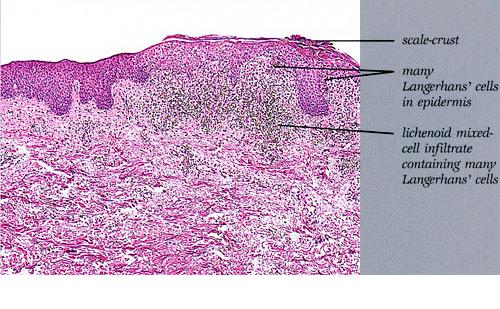

Histiocytosis X =x كثرة المنسجات